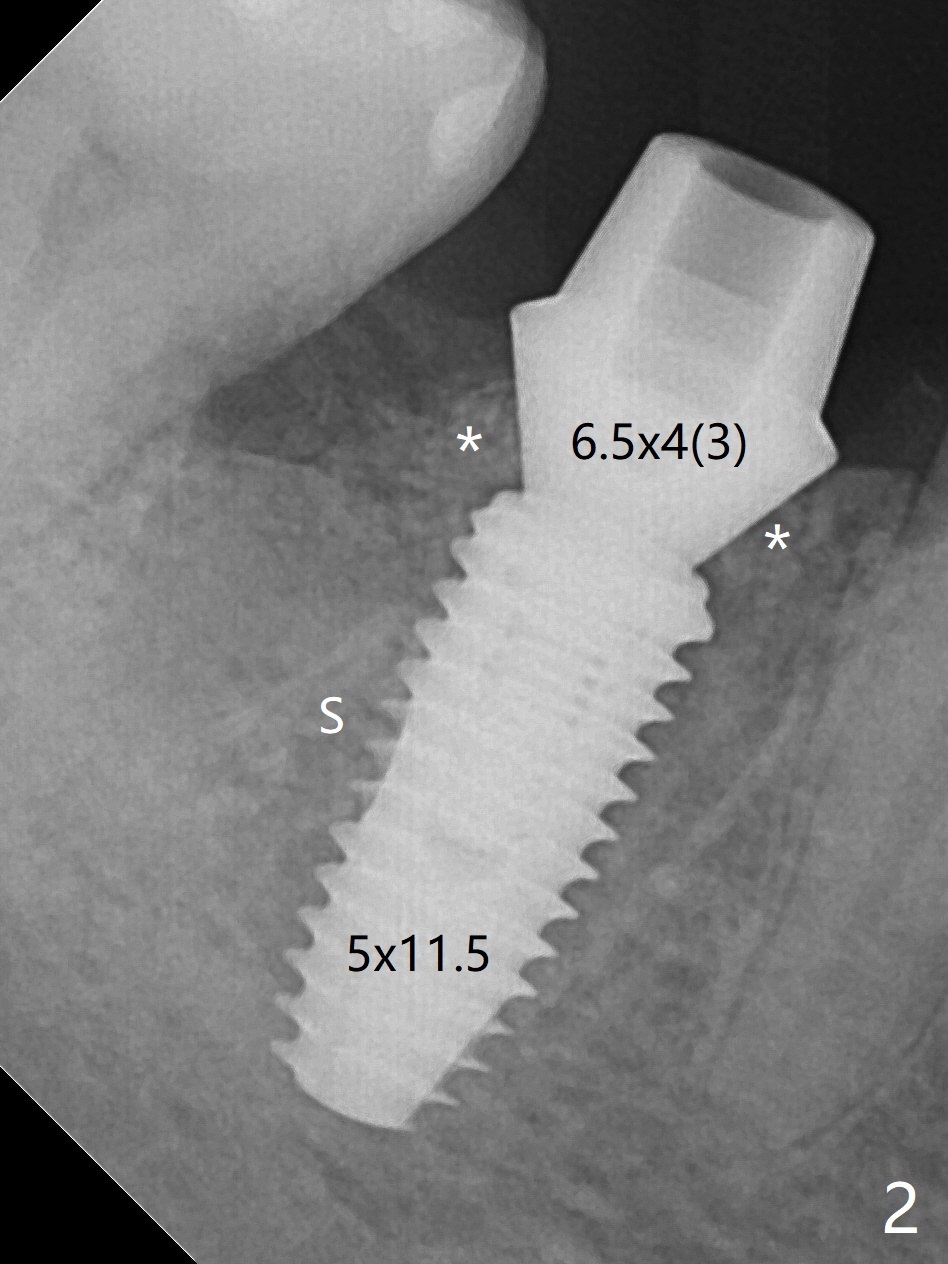

After extraction of #30 (Fig.1 (S: septum)), a 5x11.5 mm implant is placed with guide mainly in the mesial socket (mesial to the septum (S) with >35 Ncm; after immediate placement of a 6.5x4(3) mm abutment, allograft is placed (Fig.2 *). An immediate provisional is fabricated to hold the bone graft in place (Fig.3 P). To prevent micro-movement, the provisional has clearance from the opposing dentition (Fig.4 *, nonfunctional). There is not too much loss of bone graft 4 months postop (Fig.5). In fact the mesial and distal sockets heal. The implant plateau is covered with the bone 8 months post cementation (Fig.6 arrowheads ( *: addition of porcelain for the distal gingival embrasure)).